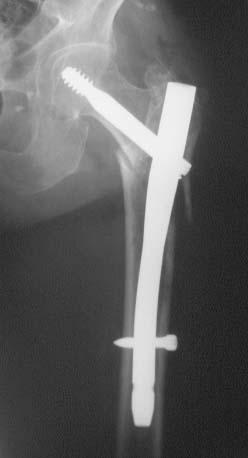

Quelques coups de téléphone plus tard, nous rejoignons le praticien hospitalier à temps plein pour commencer l'opération de pose de clou gamma sur une patiente octogénaire atteinte d'Alzheimer, qui s'est fracturée la région sous trochantérienne... sur son ancien clou gamma.

Ostéosynthèse d'une fracture trochanterodiaphysaire avec un clou gamma.